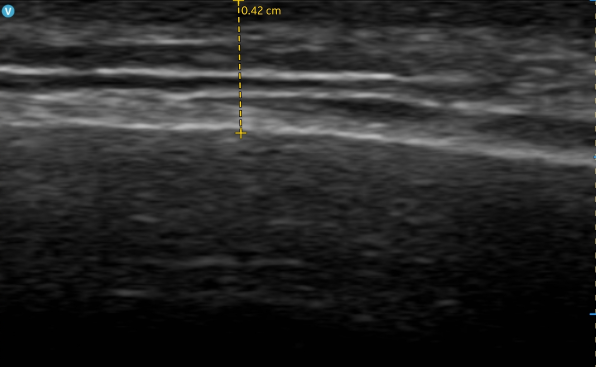

こんにちは✨<輪郭・リフティング専門>ON医院です💙💖 チタニウムリフティングとは?💖ON医院のチタニウムリフティングは、従来の高周波(RF)や超音波(HIFU)とは異なる、レーザー光を活用した新しいリフティング施術です。3つの波長(1064nm / 810nm / 755nm)を同時に照射することで、即効性のあるリフティング・タイトニング・ブライトニング効果が期待できます。✔️ 痛みが少なく✔️ ダウンタイムもほぼなし✔️ 自然なハリ・弾力・フェイスラインを即時に実感切らずに若返りを叶えたい方や、痛みに敏感な方にもおすすめの施術です。韓国・江南のON医院で人気のリフティング施術。今回ご紹介するのは、実際に施術を受けられたお客様のビフォーアフターです。📸下の写真をご覧ください。📷 Before → After(実際の症例写真)✨ 症例から分かるチタニウムリフトの効果✨✔️ 頬全体のたるみが持ち上がり、若々しい輪郭に✔️ 二重顎・フェイスラインがすっきりし、小顔効果✔️ 肌にハリと弾力が出て、ナチュラルなリフトアップON医院では、顔の状態に合わせた出力・層別の照射を行うため自然かつ高い変化が得られます。🧑⚕️ こんな方におすすめ 🧑⚕️✔️ ほうれい線や顔のたるみが気になる方✔️ リフティングと美白・肌再生を同時に叶えたい方✔️ 手術なしで、即効性のあるリフトアップを求める方✔️ ダウンタイムが少なく、自然な変化を希望する方✔️ 痛みに敏感で、施術の刺激が心配な方にもおすすめ(麻酔クリーム+出力調整可能)💡 ON医院のリフティングはここが違います💡✔️ 医学的に効果が立証されたHIFU・RFなど最新機器を使用✔️ 顔の構造に精通した医師によるカスタマイズ施術✔️ 過度な引き上げではなく、自然で調和の取れた変化を重視ON医院では、お一人おひとりのお悩みに合わせたオーダーメイドのリフティングをご提案しています。📩 ご相談・ご予約はお気軽にどうぞ。次回は別の症例もご紹介予定です。ぜひチェックしてください😊O.N医院ではお得な6月イベント開催中!ぜひ見逃さずに✨🧡グーグルマップはこちら!江南ON医院アクセス